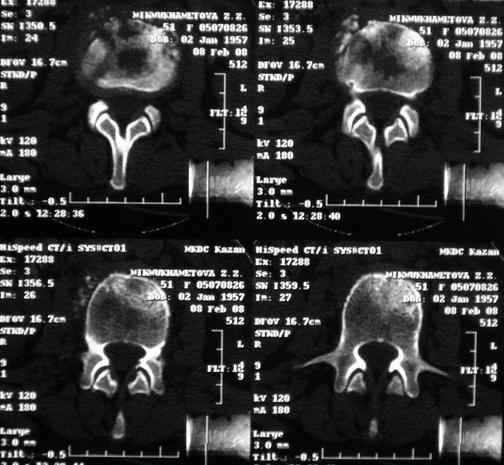

По данным представленных КТ и МРТ у больной имеется достаточно выраженная степень деструкции тел позвонков (около 30% общей костной массы тела позвонка), что определяет высокий риск возникновения патогических переломов и появления локальной кифотической деформации на этом уровне.

Судя по снимкам похоже идет речь о спинальном остеомиелите для диф диагноза стоит провести черезкожную пункционную биопсию(с помощью КТ)

Уважаемый доктор! судя по последнему МРТ процесс затрагивает соседние позвонки с переходом процесса через диск. Для туберкулёза как раз и характерна картинка "целующихся" позвонков. При бактериальном процессе диск страдает лишь вторично. Туберкулиновые пробы могут быть в пределах нормы, лёгкие - чистые. Вообще туберкулёз последнее время стал очень коварен и атипичен. Такие случаи отмечались у детей старшего возраста.